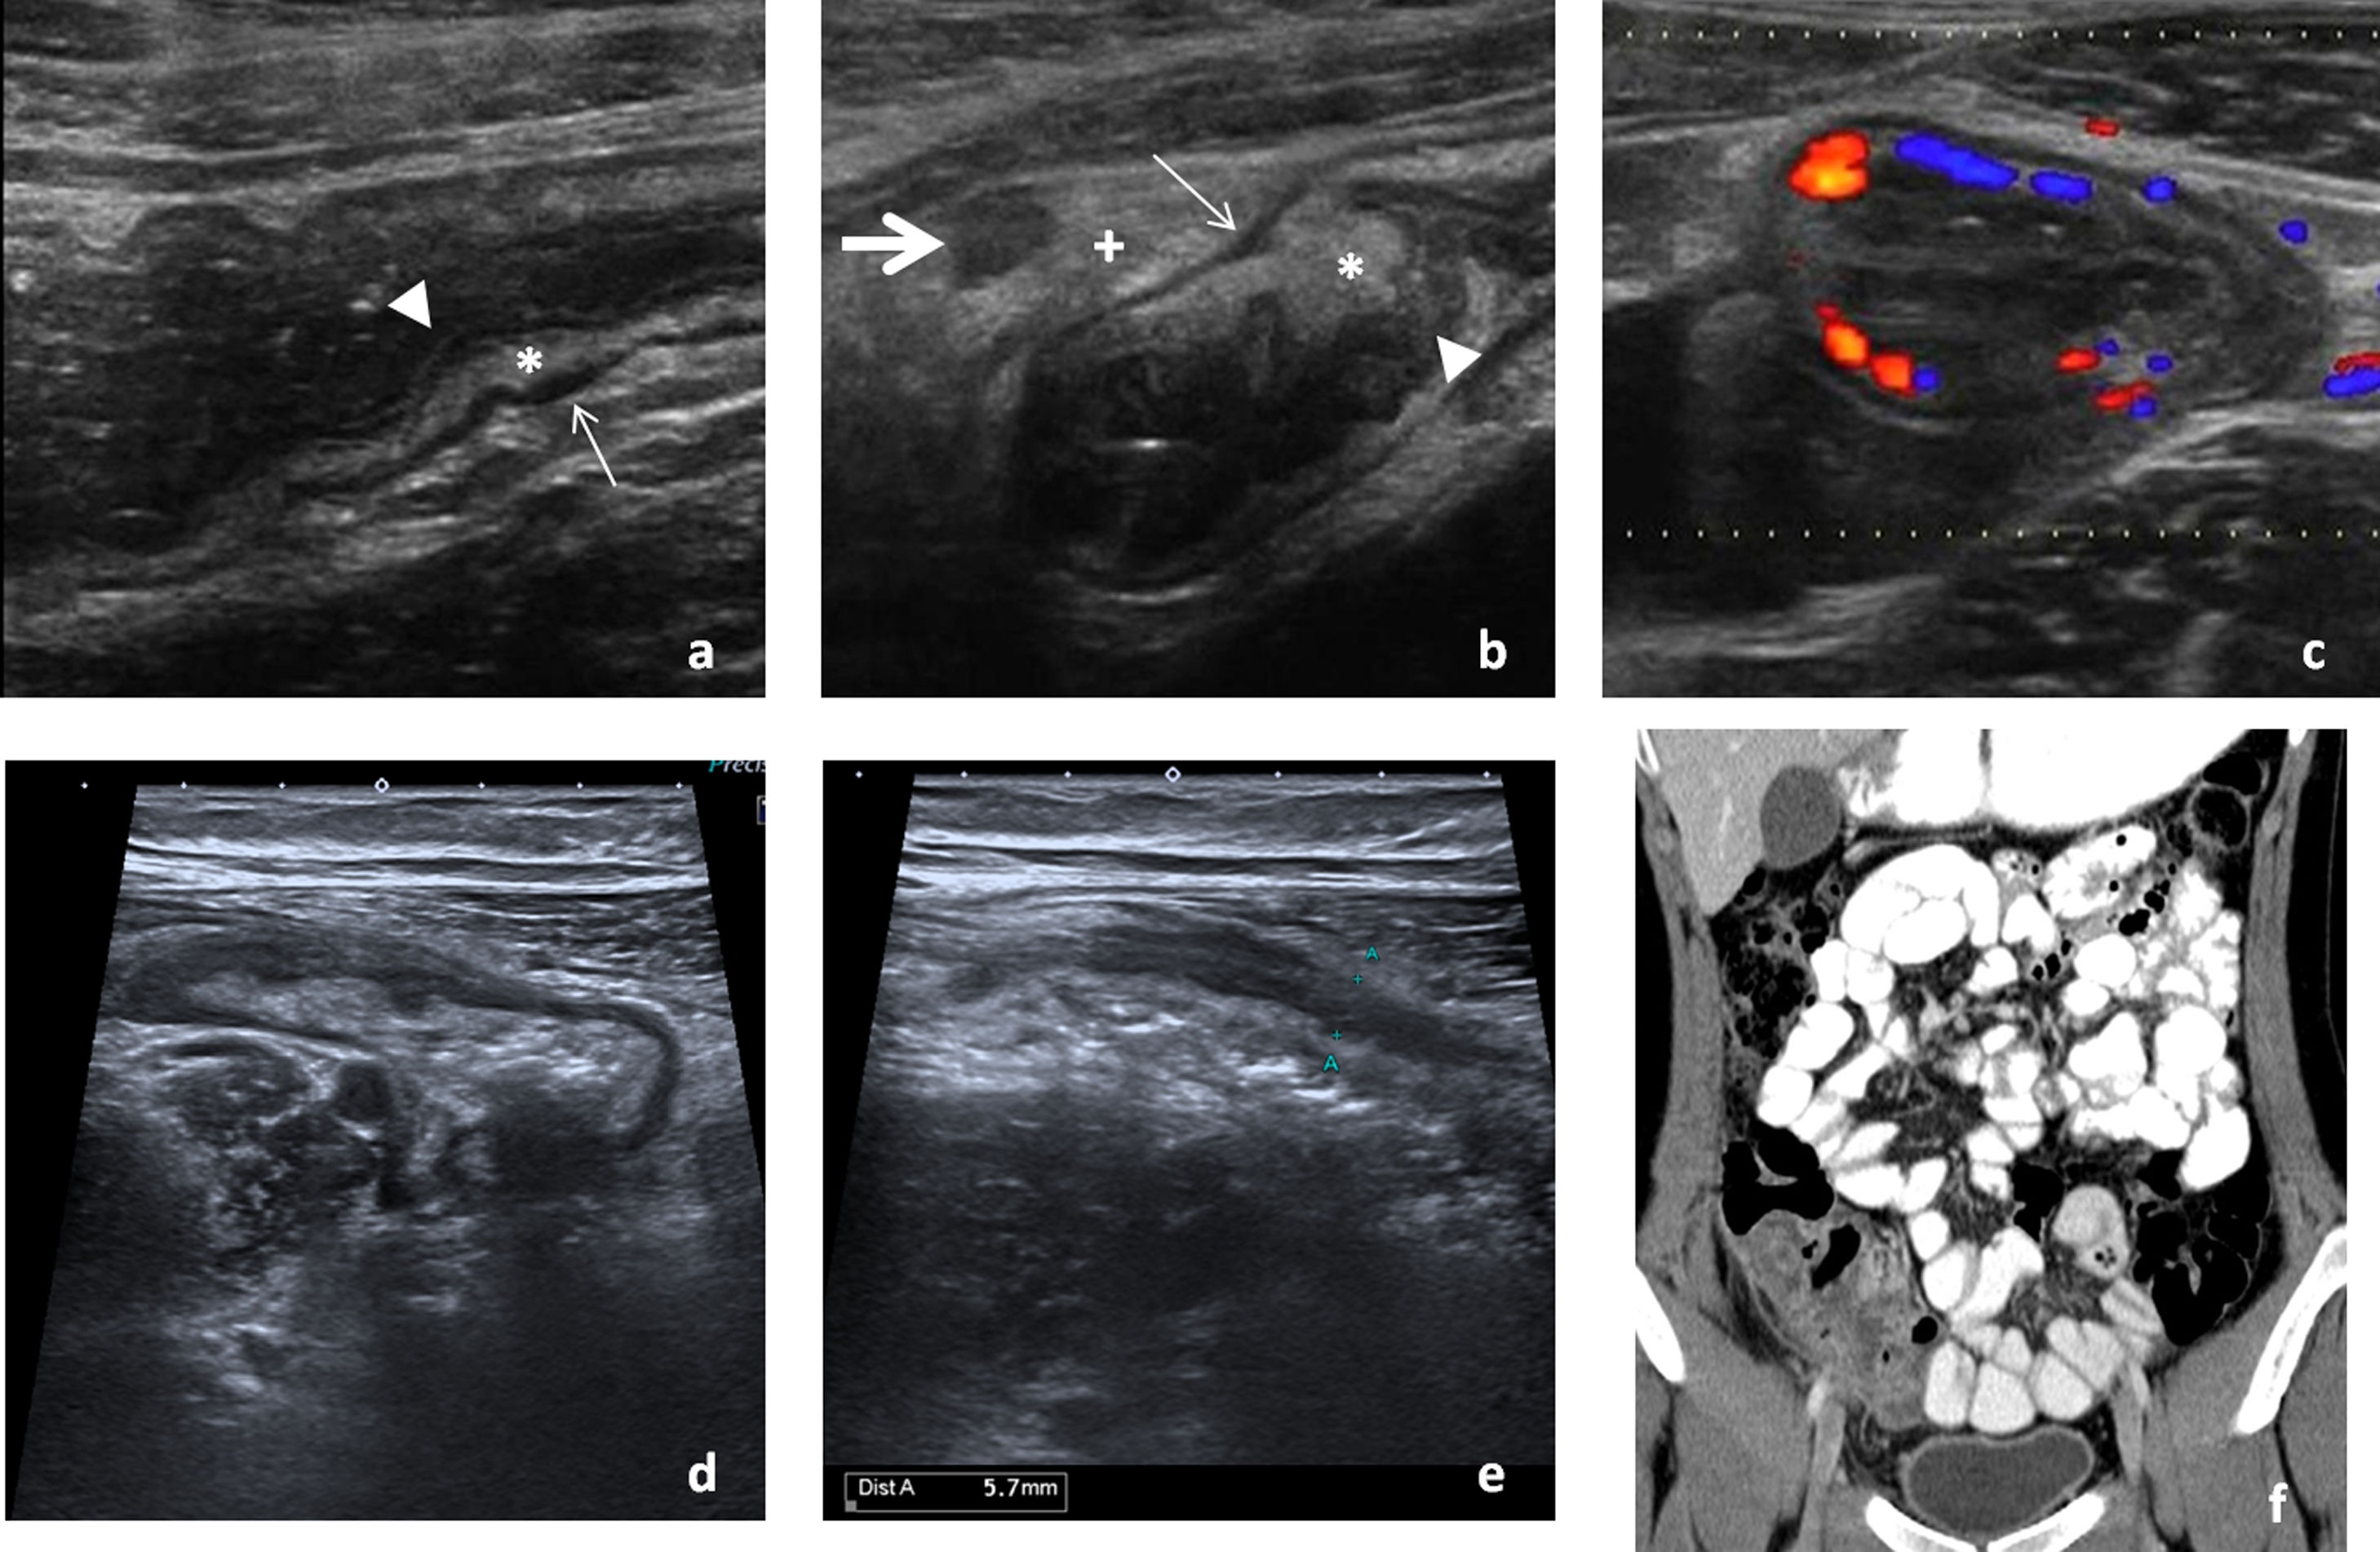

Intestino delgado distalLas infecciones del íleon terminal con frecuencia pueden extenderse al ciego (fig. 2). El principal diagnóstico diferencial es la enfermedad inflamatoria intestinal, en etapas precoces habitualmente indistinguible (tabla 2).

Afectación infecciosa del íleon distal. Primer caso de paciente joven con dolor abdominal y diarrea que consulta en el servicio de urgencias. Se realiza ecografía para filiar el origen del cuadro. Presentamos imágenes en corte longitudinal (A y B) del íleon terminal, objetivando un engrosamiento de la pared que conserva la estratificación de sus capas, afectando a la capa mucosa (cabezas de flecha) y submucosa (*) y respetando la capa muscular (flechas finas), característico de las enteritis infecciosas frente a otras causas de afectación intestinal. El estudio mediante Doppler color muestra un aumento de la vascularización secundaria al cuadro infeccioso (C). Se acompaña de tumefacción e hiperecogenicidad de la grasa mesentérica adyacente (+) y un ganglio ileocólico aumentado de tamaño de naturaleza reactiva (flecha gruesa). El cultivo de heces resultó positivo para Yersinia enterocolitica. Tras tratamiento antibiótico y sintomático, la paciente mejoró progresivamente hasta al alta. Segundo caso de paciente de 18 años, que acude al servicio de urgencias por febrícula y dolor abdominal en fosa iliaca derecha de horas de evolución. En la valoración inicial se realiza ecografía con la sospecha de apendicitis aguda, en la que se aprecia un engrosamiento de la pared de íleon terminal que se extiende al ciego (D) y un apéndice ileocecal de calibre normal (E), que orienta a cuadro infeccioso, descartando la sospecha diagnóstica que motivó la petición. A las 24 horas, se solicita una tomografía computarizada abdominal. Mostramos una imagen de reconstrucción coronal del estudio en la zona de interés (F), que muestra los mismos hallazgos. Dada la persistencia de la clínica, se decide intervenir quirúrgicamente a la paciente, practicando una resección ileocólica con el resultado histológico de enterocolitis supurada con apéndice normal. No pudo determinarse en el estudio microbiológico el agente infeccioso que originó el cuadro.